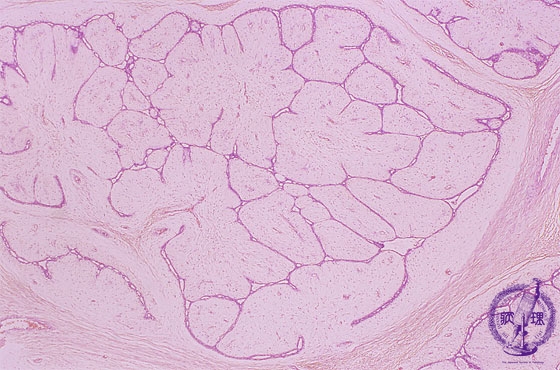

• š(2)Fibroadenoma(intracanalicular type)

Microscopic image(HE stain, low power view):Associated with marked proliferation of stroma. Tumor epithelium proliferates within slit-like or branching spaces among fibrous/edematous stroma.